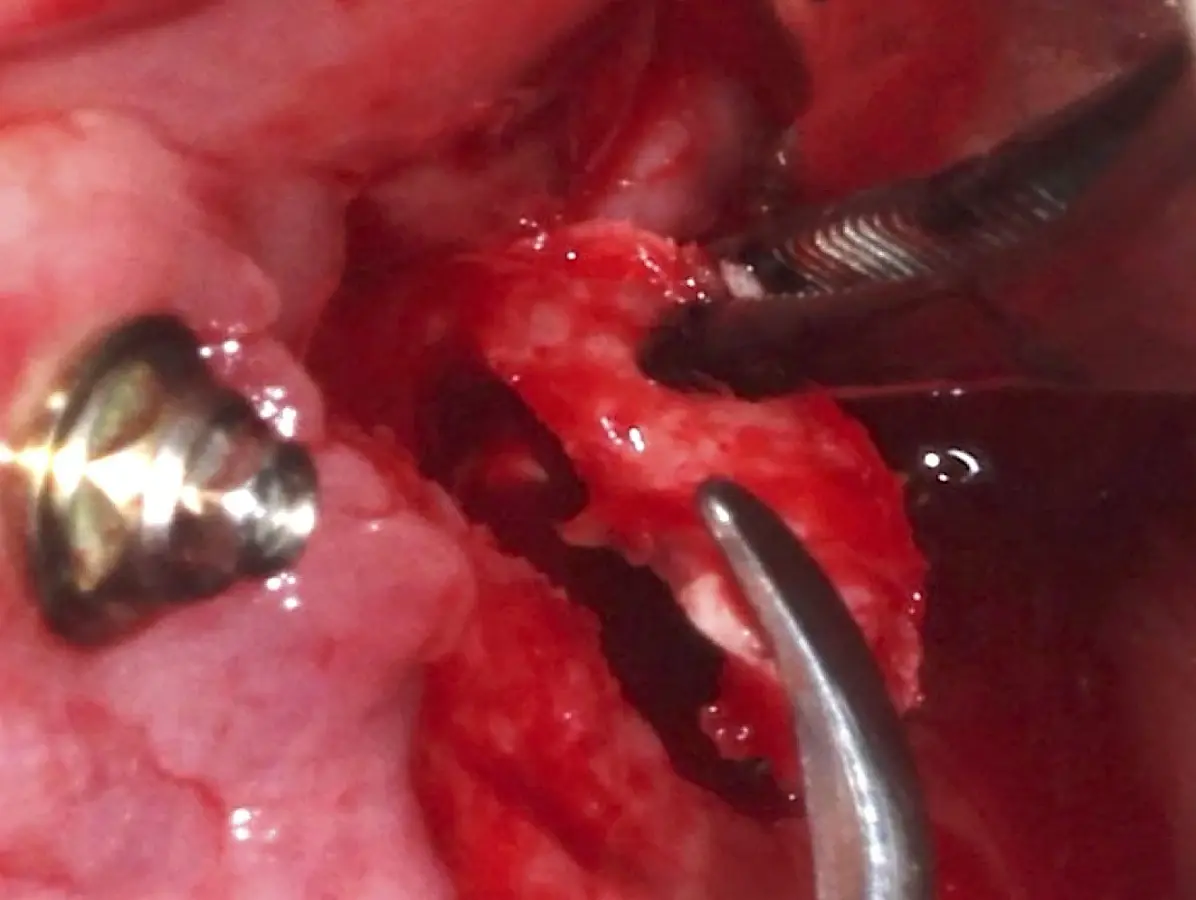

La técnica se inicia con la colocación de anestesia infiltrativa, posteriormente se realiza una incisión crestal o paracrestal con posibles liberantes verticales que deben de estar alejadas por lo menos 5 mm de los límites de la futura ventana y sobrepasar la línea mucogingival. Se realiza una elevación de colgajo, se inicia la antrostomía y antroplastía. Para ello, se emplea el inserto redondo diamantado de corte al momento de delimitar los bordes de la ventana de acceso. Luego se cambia al inserto aserrado liso de calibre fino con superficie diamantada, para profundizar y eliminar el hueso en el contorno de la ventana. Una vez que se traslucen los tejidos, se puede optar por el retiro de la tapa ósea o el levantamiento de ésta junto con la membrana.

Se inicia la elevación de la membrana de Schneider con el inserto redondeado no cortante en forma de disco, empleando movimientos suaves. El levantamiento puede complementarse con elevadores convencionales, siguiendo la dirección mesiodistal. La fase de desprendimiento inicia con el piso y sigue hacia la pared mesial para terminar, y de ser necesario, hacia la pared posterior. Existen diversos insertos con angulaciones y longitudes para mayor accesibilidad16 (Figura 1).

El tipo de inserto a ser utilizado dependerá del espesor de la pared ósea. Si la pared es menor a 0.5 mm, es mejor utilizar insertos de desgaste para prevenir la ruptura de la membrana de Schneider; si el espesor es mayor a 0.5 mm, se puede utilizar insertos de corte de espesor medio (Figura 3).